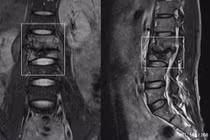

Lao cột sống thường xuất hiện ở đốt sống L1-L2 và D9-D12. Vi khuẩn lao âm thầm phá hủy các thân đốt sống nên ngoài triệu chứng đau vùng đốt sống, người bệnh có thể sốt nhẹ về chiều, chán ăn, giảm cân, cơ thể ốm yếu, mệt mỏi.